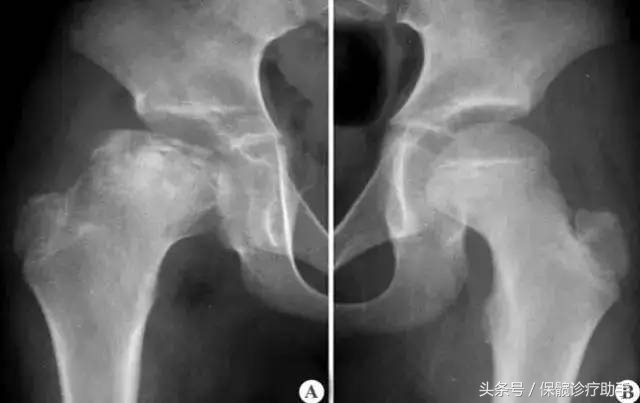

关键词2:股骨头骨骺缺血性坏死

股骨头骨骺缺血性坏死,又称儿童型股骨头骨骺软骨缺血及扁平髋,这是一种儿童时期的髋关节自限性疾病。

病理特征:

股骨头骨化中心缺血性坏死,该病常见于3~12岁儿童,以5~7岁者居多,多为单侧病变,仅15%累及双侧股骨头,与种族及家族遗传有一定的相关性,病程为4~36个月。

主要表现:

跛行,股内侧、腹股沟区及膝内侧疼痛。